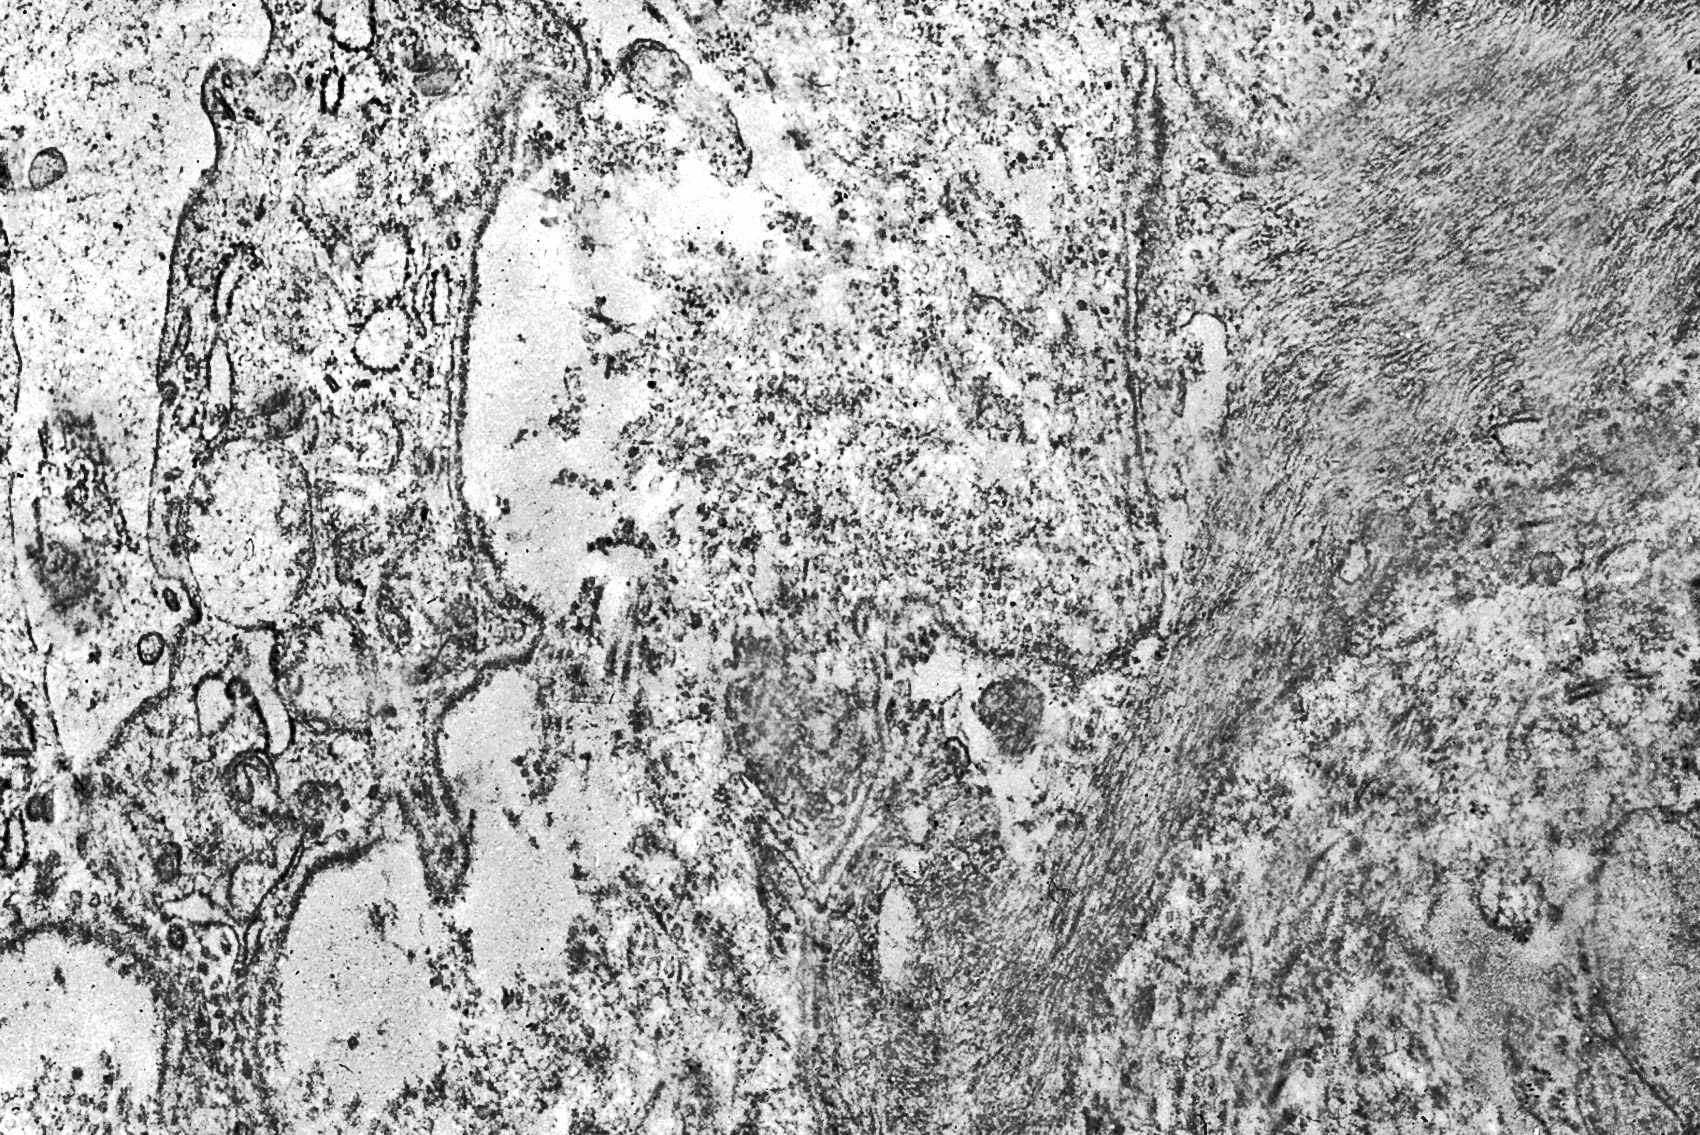

Fig.15